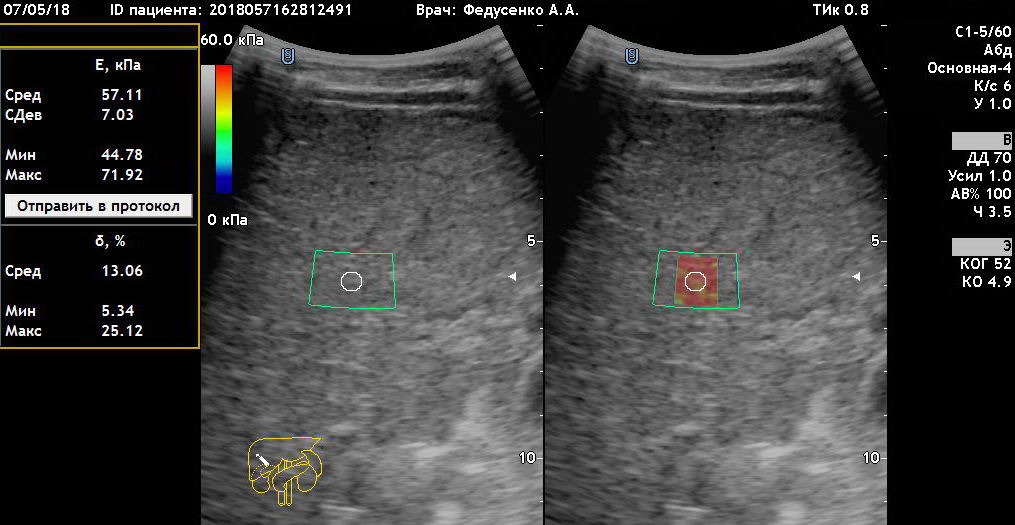

Эластометрия печени. Покажет то, что не видно на УЗИ и в анализах.

УЗИ органов брюшной полости, хорошая визуализация. Ну как тут не поизучать сегменты печени:)

УЗИ органов брюшной полости и эластография печени на Mindray Resona i9